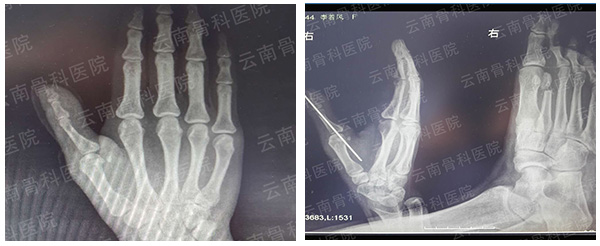

拇指Ⅳ度再造

拇指Ⅴ度再造